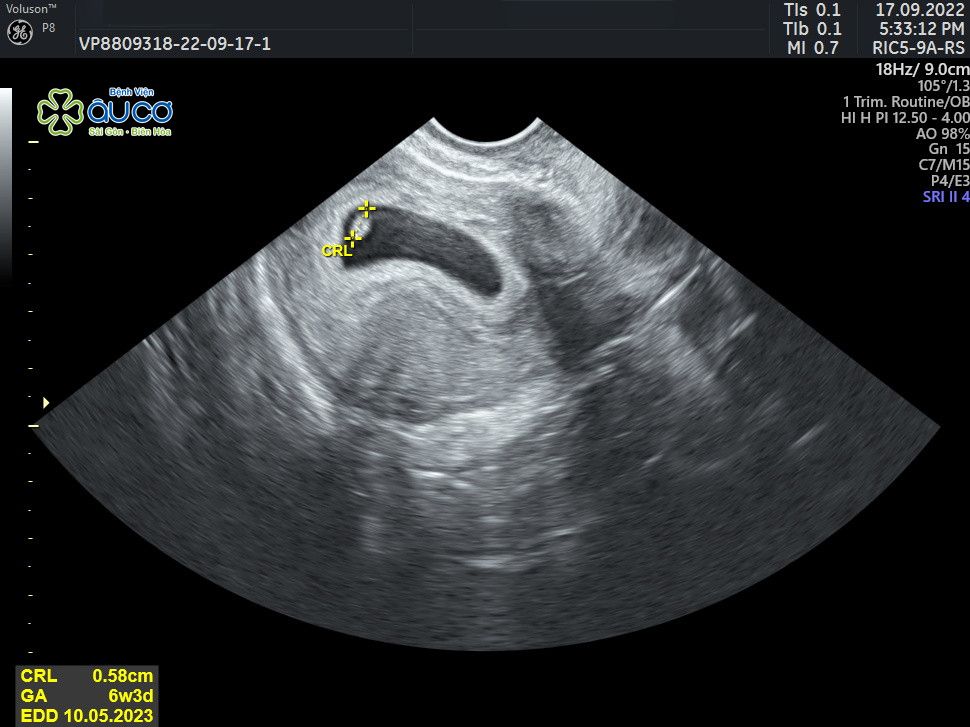

* Những hình ảnh siêu âm đáng yêu nhưng không kém phần nghịch ngợm của con qua các mốc thời gian:

![]() |

| 6 tuần 3 ngày |